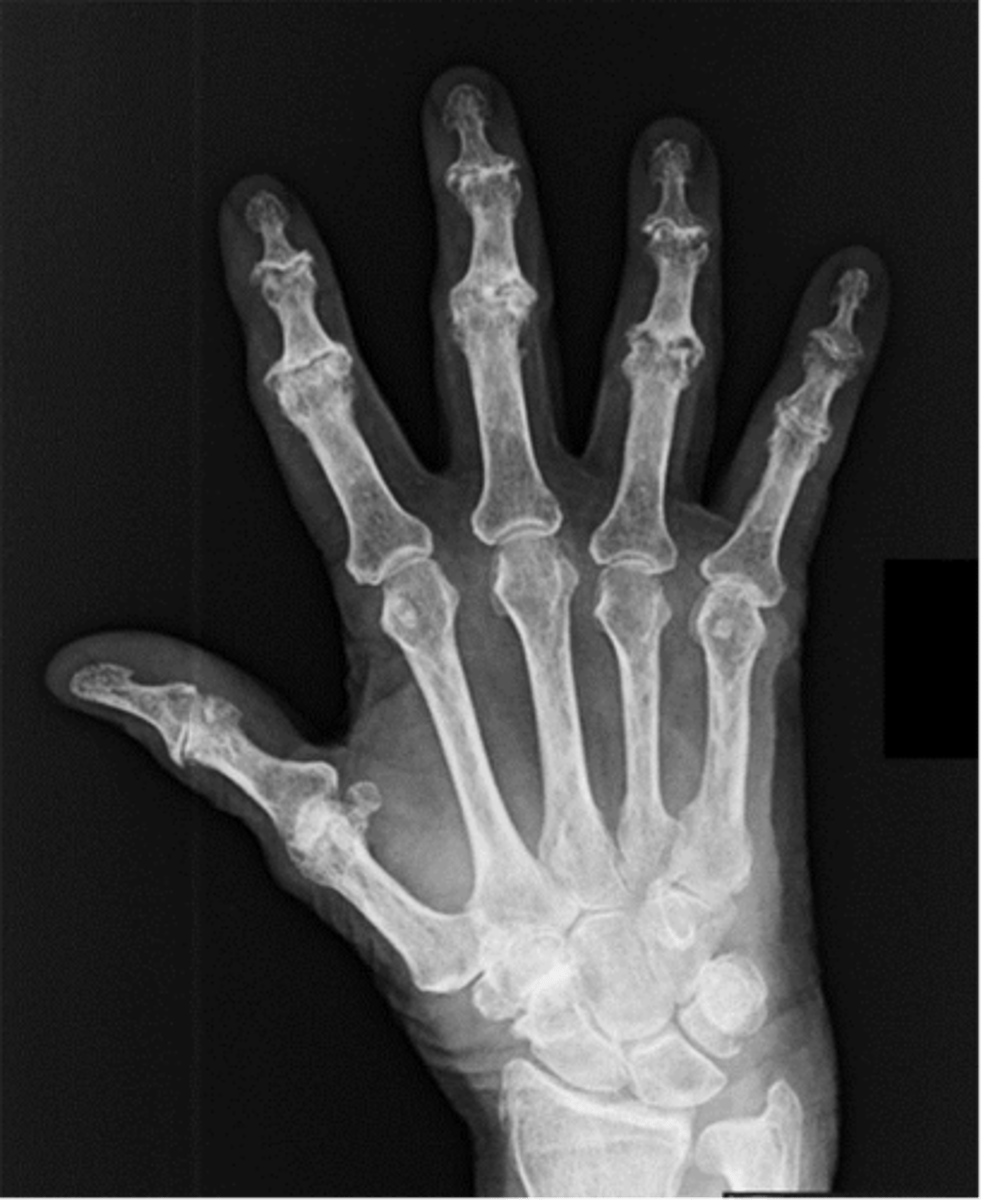

PA hand

PA oblique hand

lateral hand (extension)

Fan lateral hand

Ap oplique Bilateral hands

osteoarthrosis

Osteoporosis